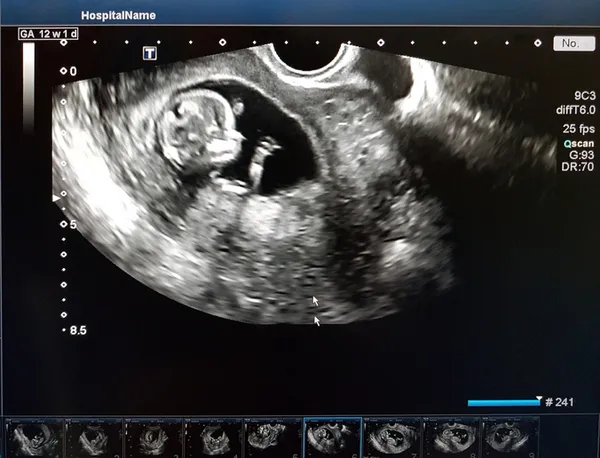

Kadın Hastalıkları, Doğum ve Perinatoloji Uzmanı Prof. Dr. Zehra Neşe Kavak; düşüğün, tıp dilinde ‘abortus’ olarak tanımlandığını belirterek, “Düşük, hamileliğin 20’nci haftasından önce sonuçlanması, yani bitmesidir. İlk 20 haftadaki kayıpları ‘düşük’ diye tanımlıyoruz. Gebelik 40 haftalık bir süreçtir. 20’inci haftadan sonra olursa olay erken doğuma girer. Diğer bir tanımı da 500 gramın altındaki bebeğin kaybıdır” diye konuştu.

Hamileliklerin yaklaşık yüzde 15-25’inin düşükle sonuçlanabildiğini, neredeyse 4 gebelikten birinde düşüğün görüldüğünü söyleyen Prof. Dr. Kavak, şöyle dedi: “Düşükle sonuçlanan hamilelikte bebekler, genellikle sağlık açısından sorunlu olabiliyor. Aslında bu doğanın doğal bir seleksiyonu. Düşüklerin yüzde 60’ının nedeni, bebekteki kromozomal problemlerdir. Bebeğin yapısında genetik bir problem vardır. Düşüklerde ikinci sırada ise bilinmeyen nedenler gelmektedir. Her 100 düşükten 30’unun nedeni bulunamıyor. Çok küçük bir oran annenin enfeksiyonları nedeniyle görülür ama bunlar tekrarlayan düşük nedeni kabul edilemez. Annenin karnına gelen bir darbe gibi direkt travmalar ya da yumurtalıklarda ortaya çıkan tümörler gibi indirekt travmalar, tiroit hastalıkları da düşük nedeni olabilir. 30 yaş üstü kadınların bebeklerinde kromozomal problem riski çoğalır. Dolayısıyla düşüklerin görülme sıklığı da artar.”